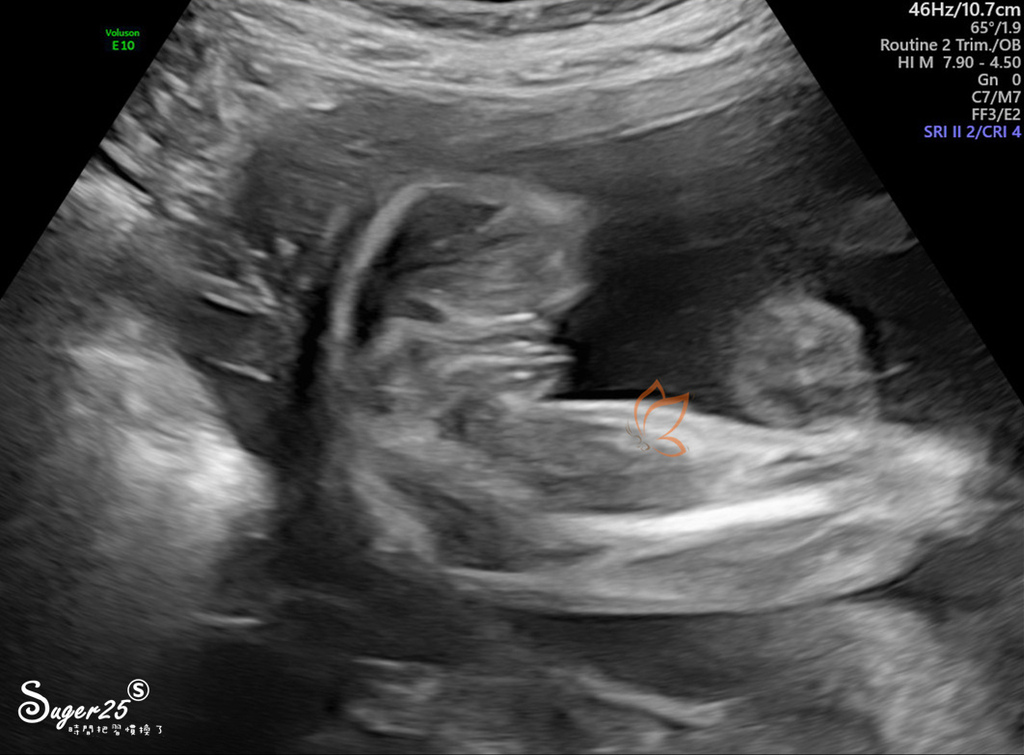

先做陰道超音波,看子宮長度

後面就是一直照肚子的高層次超音波摟!

躺在床上,有投影在天花板,可以看到超音波的畫面

張醫生來會大致上照一圈,一來馬上就開獎 : 是妹妹喔! 我覺得醫生比較用力一點點,但還可以接受的力道

後來就換成放射師幫我照,一一截圖,放射師比較溫柔一些

照的真的很仔細,從頭到腳,還有身體所有器官、靜脈動脈...等,左右兩邊的手跟腳

大腦小腦~子宮頸長度

大致上寶寶都算合作,而且很有活力踢來踢去,放射師說很會踢喔!